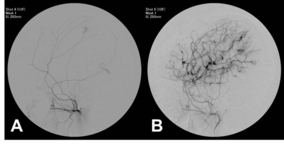

서울대 어린이병원, 모야모야병 어린이 1,000명 수술